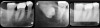

Some representative radiographic PSP images are exhibited here for demonstration of the anatomy and pathology that can be visualized with this technology. Many of these images would not have been possible if HW technology were used (Figure 3 through Figure 8).

As displayed here, the 2D radiographic images in Figure 3 through Figure 8 can alert the clinician to the need for a further 3D CBCT analysis to properly ascertain the anatomy and extent of the pathology that is initially visible in the intraoral radiographs. Proper treatment or referral to the appropriate specialty practice can follow.5,6 No. 2 PSP radiographs, when used in a conventional full-mouth series of radiographs on a patient with a relatively complete dentition, will routinely allow visualization of the anatomy of third molars, mandibular canal, maxillary sinuses, full dental root morphology, and bone anatomy beyond the apices2,16,17 (Figure 9 and Figure 10).

Fig 3. Two PSP PA radiographs of mandibular teeth showing: left, the initial view

of molar area and suspected pathology surrounding impacted tooth No. 32; center,

subsequently exposed PA radiograph, placed more distally, demonstrates extent

of large cyst as well as entire tooth and root No. 32. Proper alert as to presence

of suspected cyst and appropriate referral for 3D CBCT study and surgical

enucleation was given to the patient. Right: Same radiograph as on the left, but

with lighter superimposed outline of the area that would be visible using an HW

sensor rather than a PSP sensor. The small area of pathology is likely obscured

because it is visually overlaid by the root of tooth No. 31. Neglect of this significant

pathology may have resulted.

Figure 3